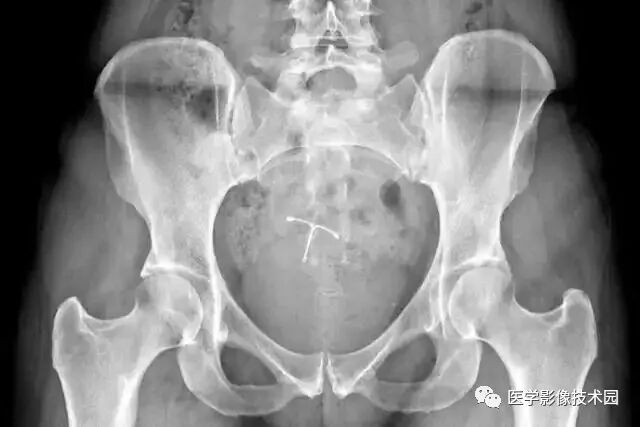

(4)有宫内节育器者不能做盆腔检查;